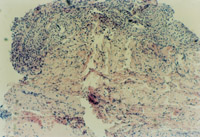

3-23 對(duì)其“皮點(diǎn)”進(jìn)行組織學(xué)檢查,該組織為從皮下組織中再生出的微血管、膠原組織、表皮細(xì)胞組織組成的再生皮膚組織團(tuán)